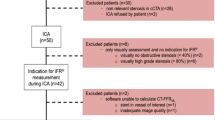

To evaluate the impact of an iterative reconstruction (IR) algorithm (advanced modeled iterative reconstruction, ADMIRE) on machine learning-based coronary computed tomography angiography–derived fractional flow reserve (CT-FFRML) measurements compared with filtered back projection (FBP). 170 plaque-containing vessels in 107 patients were included. CT-FFRML values were measured and compared among 5 imaging reconstruction algorithms (FBP and ADMIRE at strength levels of 1, 2, 3 and 5). The plaques were classified as, ‘calcified” or “noncalcified” and “≥ 50% stenosis” or “< 50% stenosis’, a total of four subgroups by consensus. There were no significant differences of CT-FFRML values among the FBP and ADMIRE 1, 2, 3 and 5 groups wherever comparisons were done at the level of subgroups (P = 0.676, 0.414, 0.849, 0.873, respectively) or overall (P = 0.072). There were 20, 21, 19, 19 and 29 vessels with lesion-specific ischemia (CT-FFRML ≤ 0.80) in FBP and ADMIRE 1, 2, 3 and 5 datasets, respectively, but no statistical differences were found (P = 0.437). Compared with CT-FFRML value of FBP dataset, the CT-FFRML values of 9 (5.3%) vessels from 8 patients (7.5%) in ADMIRE5 dataset switched from above 0.8 to below or equal to 0.8. There were no significant differences of the CT-FFRML values among the FBP and IR image algorithms at different strength levels. However, high iterative strength level (ADMIRE 5) was not recommended, which might have an impact on diagnosis of lesion-specific ischemia, although changes only occurred in a modest number of subjects.